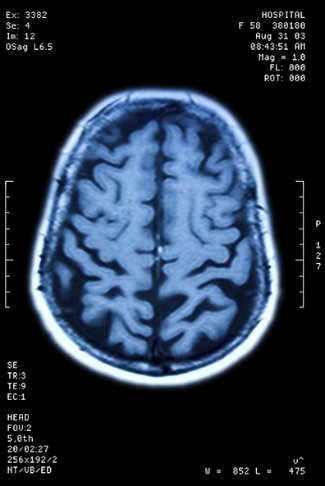

The two Alzheimer’s medications approved by the FDA have proven effective for some individuals in the early stages of the disease by targeting amyloid plaque that builds up in the brain of affected people. But Dr. Kiran Bhaskar, professor in the Department of Molecular Genetics & Microbiology at the University of New Mexico’s School of Medicine, believes another approach may offer even greater health benefits.

“In addition to removing amyloid with those FDA-approved drugs, it is essential to remove another protein, tau, which accumulates as tangles in the brain and more closely mirrors the location of areas of the brain that deteriorate and shrink as Alzheimer’s progresses,” he said.